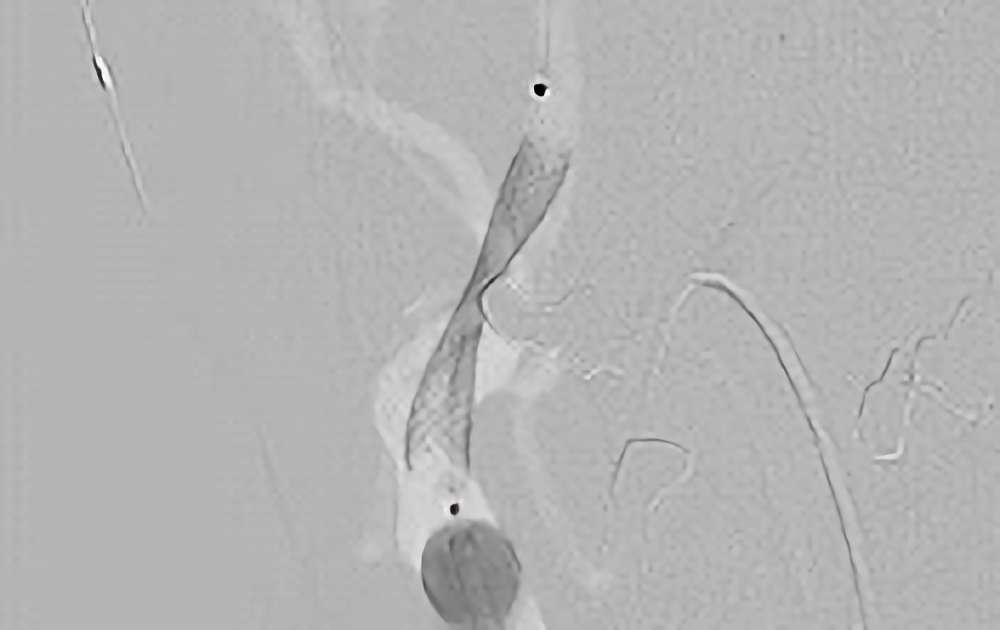

859

'20年7月20日

右内頚動脈狭窄症

70代

大阪府の病院

手術写真

治療

前

中

後

手術日